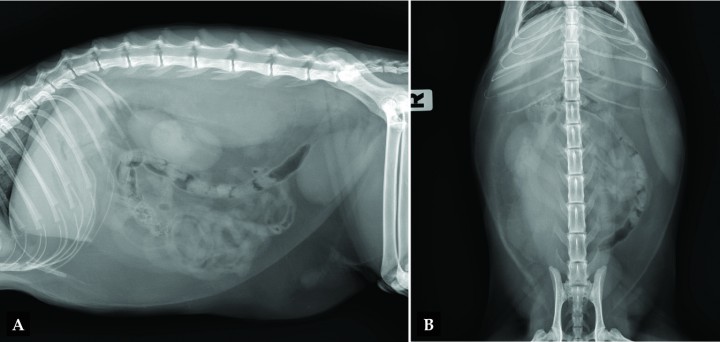

Se realizan radiografías de abdomen lateral (L) y ventrodorsal (Fig. 1) para investigar posibles causas del dolor abdominal y la fiebre asociada.

(A) Radiografía lateral y (B) ventrodorsal de abdomen de un gato que se presenta con dolor abdominal.

El paciente presenta buena definición de serosas gracias al abundante tejido adiposo intraabdominal (Fig. 2). El tracto gastrointestinal tiene un patrón de contenido gaseoso-mucoso, con heces formadas en intestino grueso sin tramos de distensión patológica. El bazo presenta un incremento marcado de tamaño, con bordes regulares redondeados, silueta y opacidad homogéneas en la pared izquierda del abdomen (asterisco), ocupando una posición más ventral de lo esperado debido a su incremento de tamaño.

Podemos apreciar una opacidad tejido blando con bordes homogéneos y bien definidos lateral y ventralmente, con signo de silueta positivo asociada al dorso de la cavidad abdominal (flechas amarillas), que desplaza ambos riñones ventralmente (el derecho también lo desplaza lateralmente, visible en la proyección VD), así como el borde caudodorsal de los lóbulos pulmonares caudales (flecha naranja). La opacidad se extiende por la porción derecha del tejido blando paraespinal desde el nivel de la T12 hasta L7. No se aprecian signos de reactividad ósea asociados a la opacidad tejido blando. El resto de la exploración no presenta alteraciones significativas.